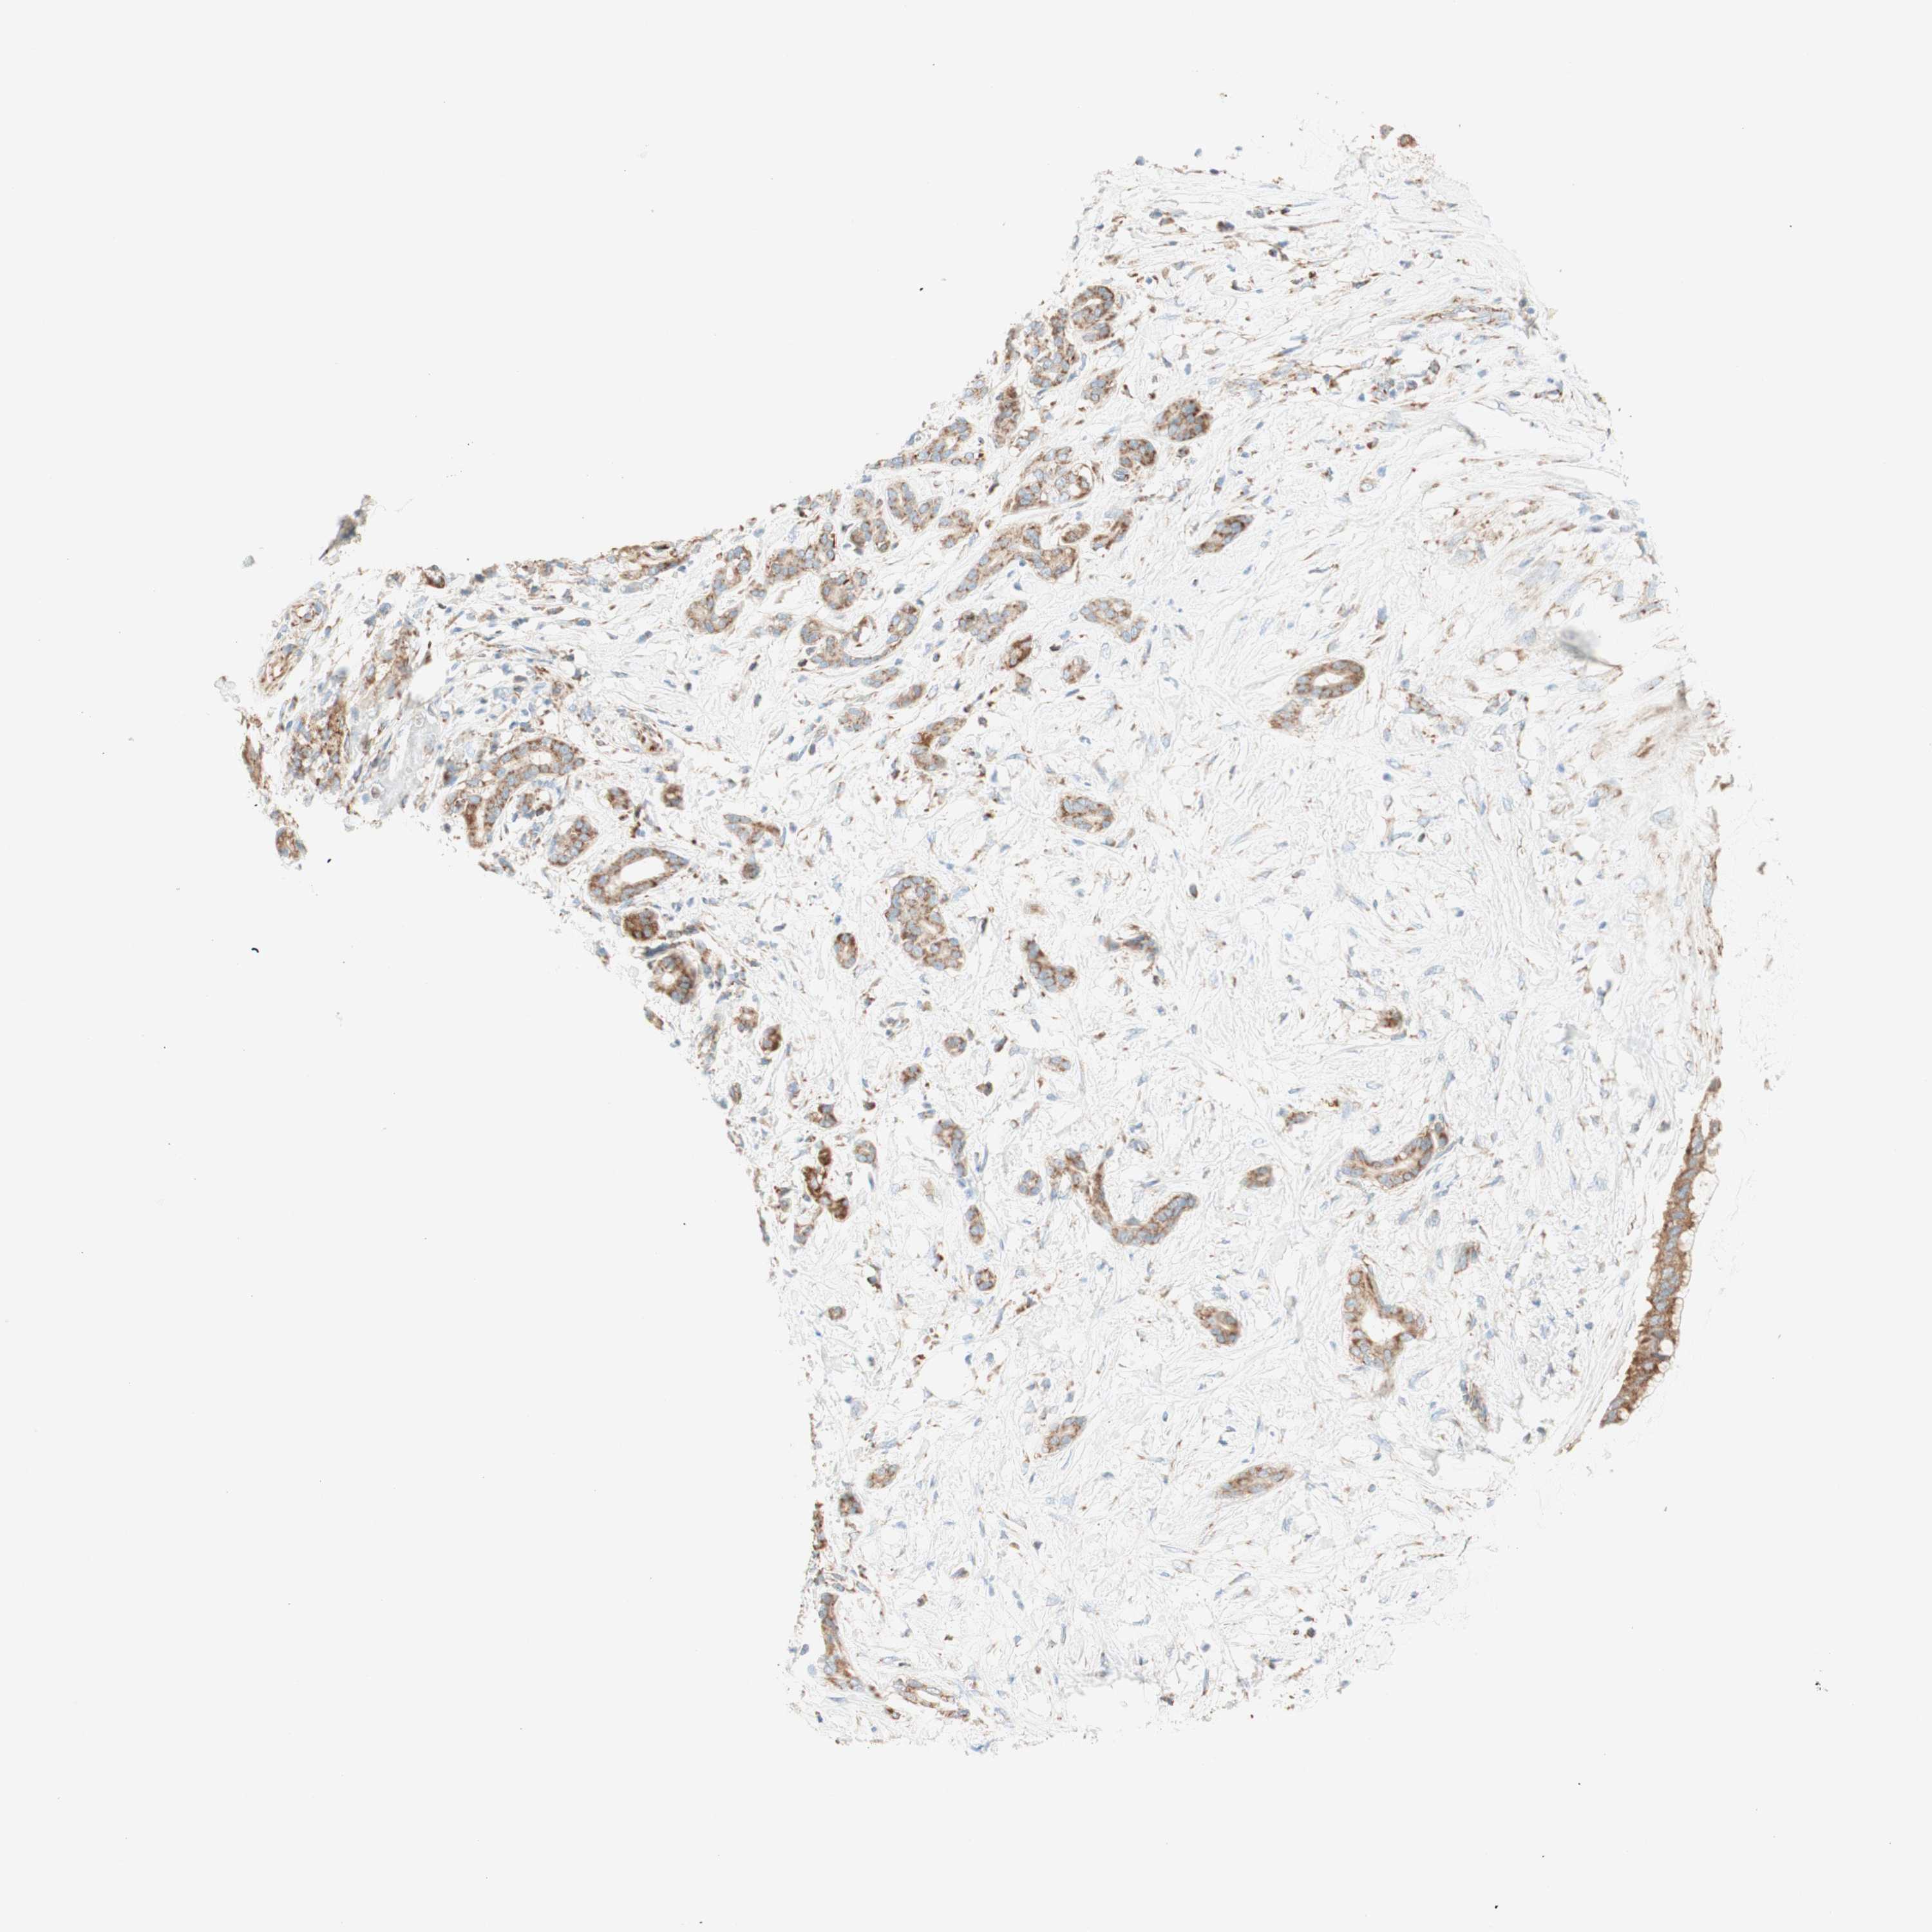

PANCREATIC CANCER - Protein expressioni

A mouse-over function shows sample information and annotation data. Click on an image to view it in a full screen mode. Samples can be filtered based on level of antibody staining by selecting one or several of the following categories: high, medium, low and not detected. The assay and annotation is described here.

Note that samples used for immunohistochemistry by the Human Protein Atlas do not correspond to samples in the TCGA dataset.

Antibody stainingi

Antibody staining in the annotated cell types in the current human tissue is reported as not detected, low, medium, or high, based on conventional immunohistochemistry profiling in selected tissues. This score is based on the combination of the staining intensity and fraction of stained cells.

Each image is clickable and will lead to virtual microscopy that enables deeper exploration of all samples and also displays staining intensity scores, fraction scores and subcellular localization as well as patient and tissue information for each sample.

Antibody HPA011562

Antibody CAB005585

Staining

High

Medium

Low

Not detected

Intensity

Strong

Moderate

Weak

Negative

Quantity

>75%

75%-25%

<25%

None

Location

Nuclear

Cytoplasmic/membranous

Cytoplasmic/membranous,nuclear

Adenocarcinoma, NOS

Adenocarcinoma, metastatic, NOS